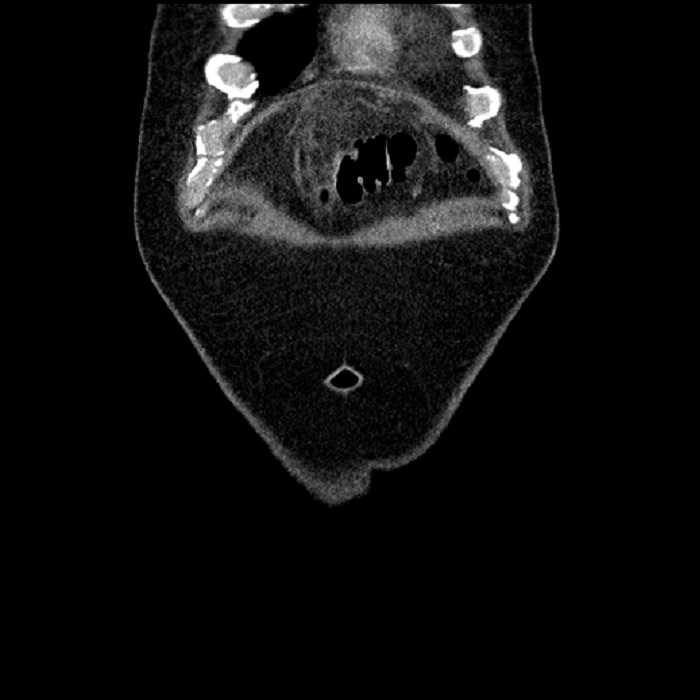

Age: 63

Sex: Male

Indication: Abdominal pain

• Large fluid density structure in hepatic segments 7 and 8 measuring 10 x 7 x 7 cm with internal septation and circumferential ill-defined low density compatible with edema

• Peripherally enhancing subcapsular collections along the anterior margin of the left hepatic lobe measuring 3 x 1 cm and 2 x 1 cm

• Clearly marginated fluid density structure in segment 7 and several other scattered tiny hypodensities, which likely represent cysts

• Hepatic abscess

Acute sigmoid diverticulitis complicated by a small contained perforation and a large abscess in the right hepatic lobe. Additional small subcapsular abscesses along the anterior margin of the left hepatic lobe.

Hepatic abscess showing the double target sign with low density internally surrounded by a thin inner enhancing rim (red arrow) and ill-defined outer low density rim (yellow arrow). Blue arrow indicates an internal septation. Red arrows: additional smaller subcapsular abscesses. Red arrow: focal contained perforation associated with diverticulitis.